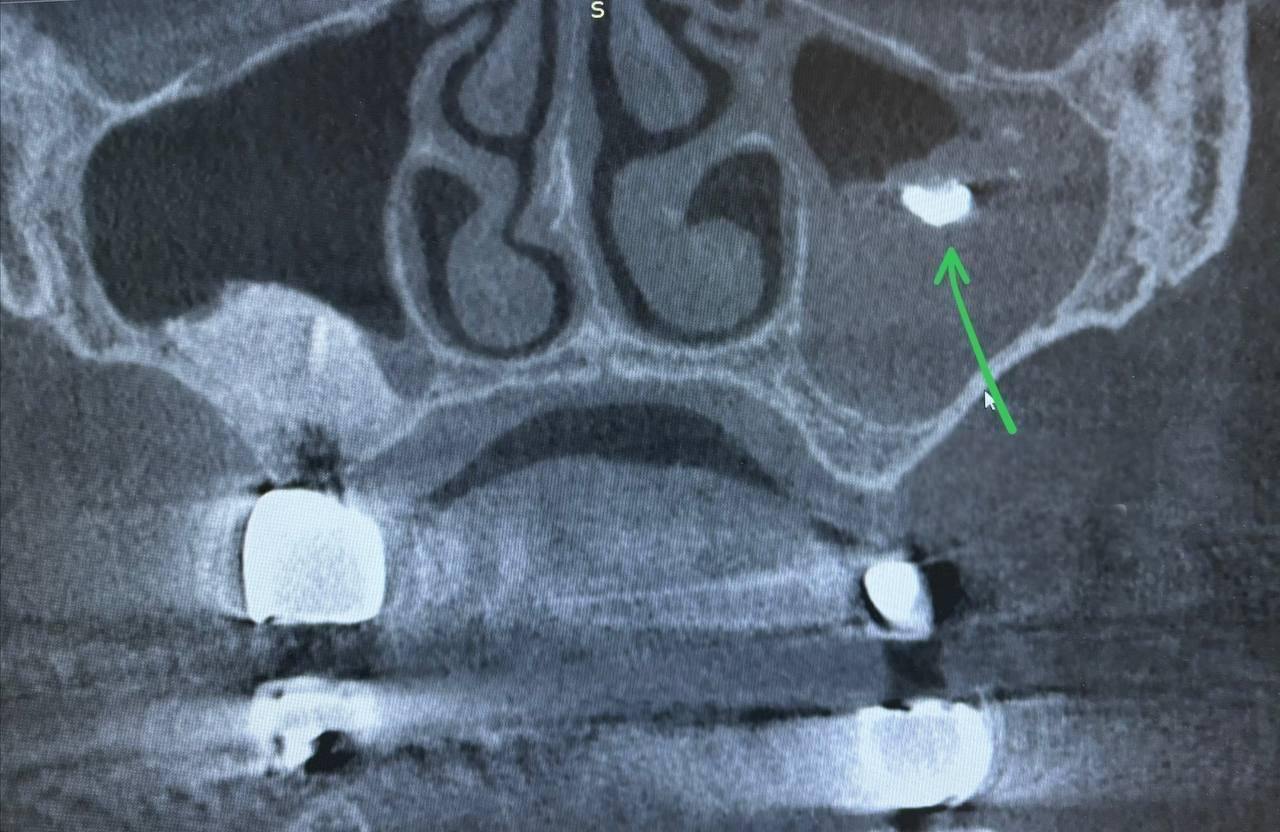

Компьютерная томография показала в верхнечелюстной пазухе инородное тело — фрагмент пломбировочного материала, который стал очагом размножения патогенных микроорганизмов.

«На первом этапе диагностики было выявлено наличие мицетомы — скопления грибковых масс внутри пазухи. В ходе эндоскопической операции стало ясно, что причиной ее образования стал именно пломбировочный материал. Все патологическое содержимое – грибковые массы и инородный пломбировочный материал — было успешно удалено. После этого пазуха была тщательно промыта антисептическими растворами для предотвращения дальнейшего развития инфекции и стимуляции процесса заживления», — рассказал врач-оториноларинолог Видновской клинической больницы Магомед Гасанов.